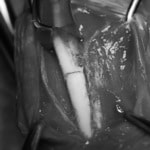

症例:交通事故による椎体脱臼

柴犬:9歳、避妊雌

交通事故直後、胸腰部に激しい疼痛、両後肢に完全麻痺を認め、シェフシェリントン徴候を呈していました。レントゲン検査において、第11-12胸椎間の脱臼が認められました。

脊髄の減圧、脊柱管の再構築・安定化を目的に、片側椎弓切除術およびMatrixMANDIBLE Plateによる椎体固定を実施しました。

隣接椎体を架橋するようにプレートを設置しました。